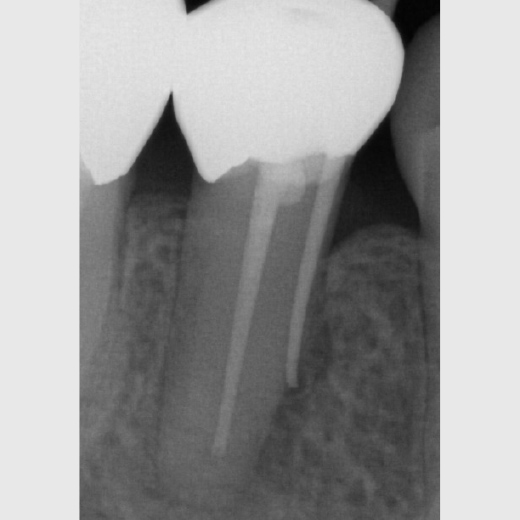

Fallbeispiel: Zahn 15 mit starker Krümmung

Jeder Zahn ist einzigartig – in diesem Fall zeigte sich Zahn 15 mit einer starke Wurzelkrümmung. Trotz der starken Krümmung konnte eine Wurzelkanalbehandlung durchgeführt werden und somit auch die Brücke erhalten werden.